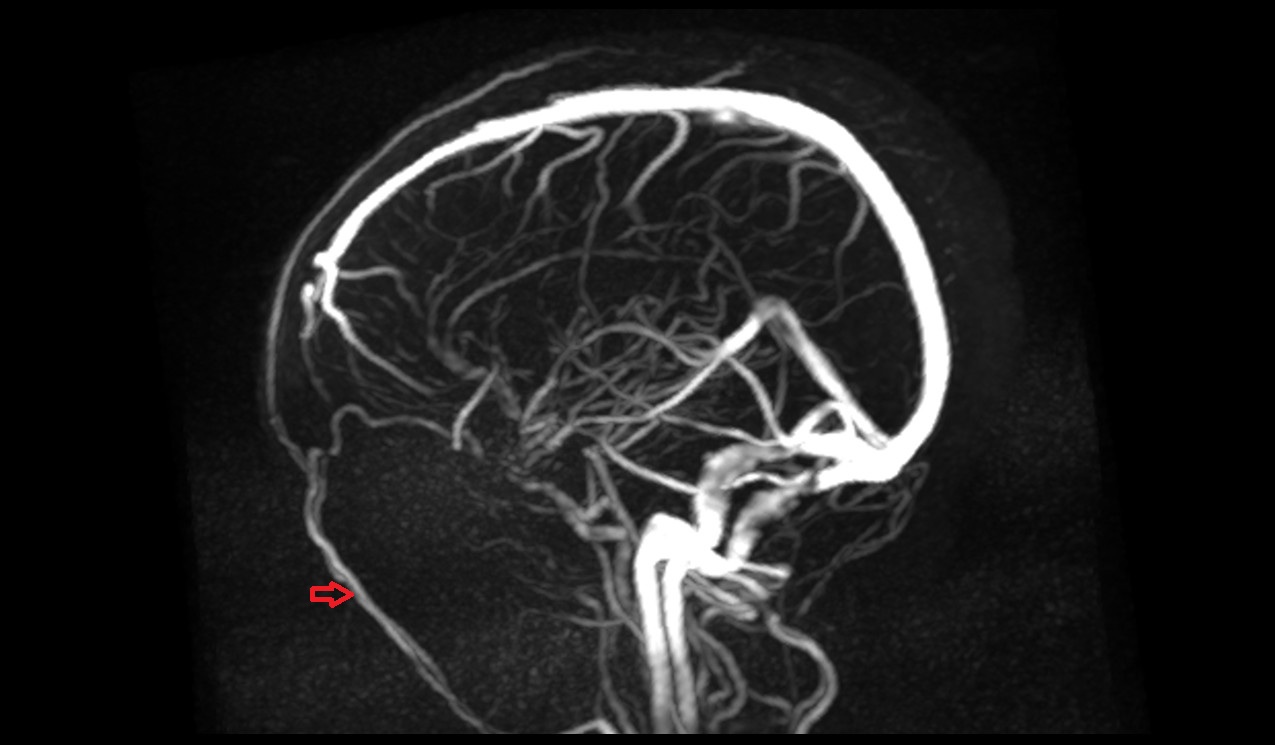

- Right vertebral artery

- Left vertebral artery

- Right Vertebral Artery (Intracranial Part)

- Left Vertebral Artery (Intracranial Part)